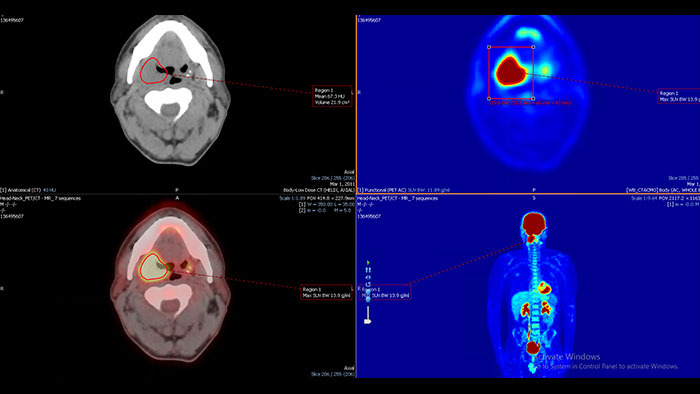

Enhanced user experience for NM reading with a leading NM viewing solution

A comprehensive NM solution, designed to enhance productivity of PET/CT and NM reading. It offers a solution for handling multiple studies requiring rigorous quantification of MV data**.

Benefits